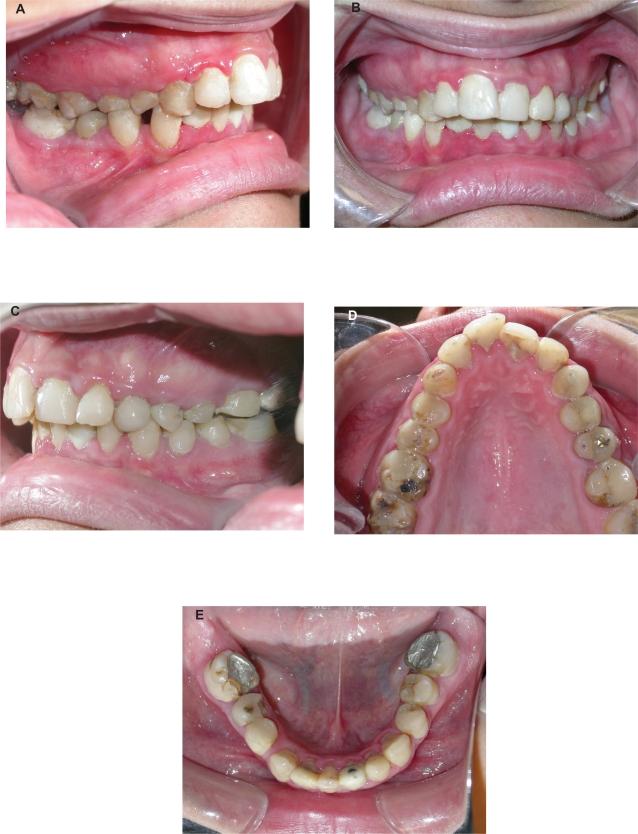

We describe the long-term complications six years after chemoradiotherapy in a 20-year old woman with nasopharyngeal carcinoma. We wanted to know whether the radiation dose was constant throughout the oral cavity, and thus uniformly affecting the corresponding dental and skeletal structures. Clinical and radiologic findings are described six years after chemoradiotherapy based on a two-dimensional computerized treatment planning system. This revealed radiation caries limited only to posterior teeth, proximal caries in the anterior teeth, limited but continuous salivary flow, mild periodontal infection, mild xerostomia, and a regenerative capacity of bones and the developmental process. The quantitative assessment of radiation delivered to the mandible revealed a high radiation dose in the posterior area and a minimal dose in the anterior area. This explains the differences in caries manifestation between the anterior and posterior teeth. According to the present study, individualized radiation fields, using a two-dimensional treatment planning system, result in restriction of severe damage of the dental and skeletal structures, which usually follows chemoradiotherapy. Orthodontic treatment could be initiated according to individual patient needs.

我们描述了一位 20 岁女性鼻咽癌患者在接受放化疗 6 年后的长期并发症。我们想知道口腔内的辐射剂量是否保持恒定,从而均匀地影响相应的牙齿和骨骼结构。根据二维计算机治疗计划系统,在放化疗 6 年后描述了临床和影像学发现。结果显示,放射性龋齿仅限于后牙,前牙邻面龋,唾液流量有限但连续,轻度牙周感染,轻度口干,以及骨骼和发育过程的再生能力。对下颌骨接受的辐射剂量进行定量评估,发现后牙区的辐射剂量较高,前牙区的辐射剂量较低。这解释了前牙和后牙龋齿表现的差异。根据本研究,使用二维治疗计划系统的个体化放射野可限制通常由放化疗引起的牙齿和骨骼结构的严重损伤。可根据患者个体需求启动正畸治疗。